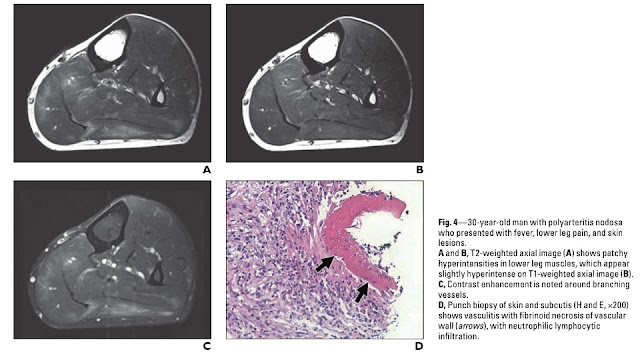

造影MRIは他の症例報告と比べてみてもそっくりな画像でした

筋生検では血管炎の所見を証明することはできませんでしたが、

採取した部位が浅すぎて、血管炎を起こしている血管を拾えなかった可能性はあります